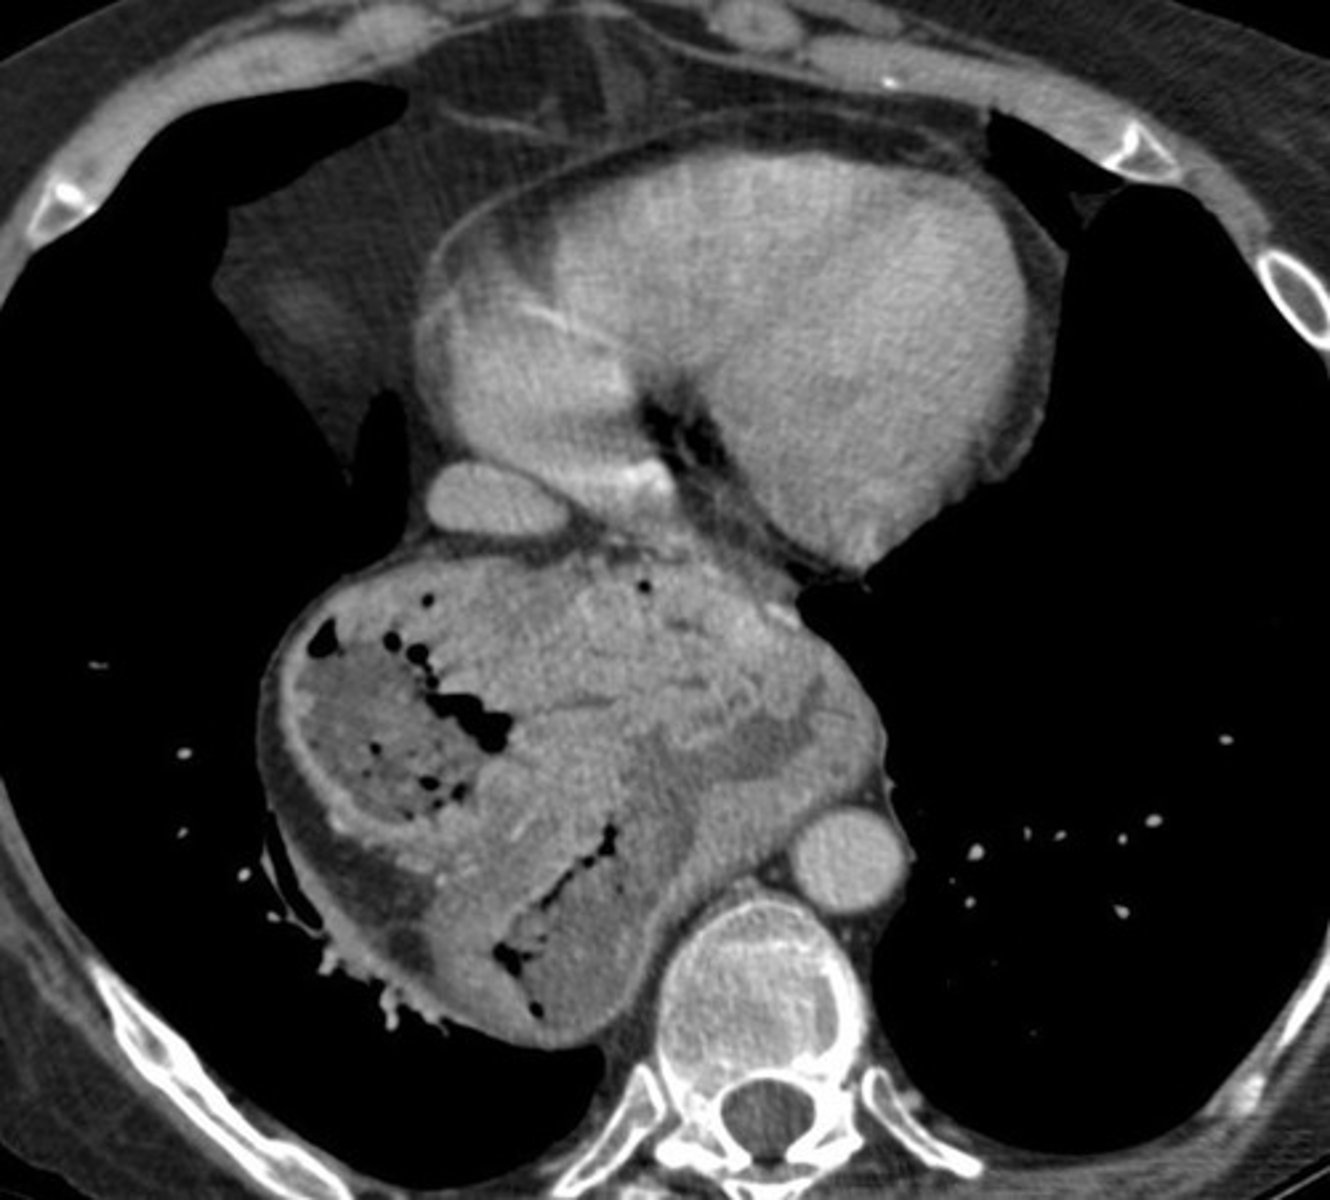

Paraesophageal hernia CT

Paraesophageal hernia CT (pic 2)